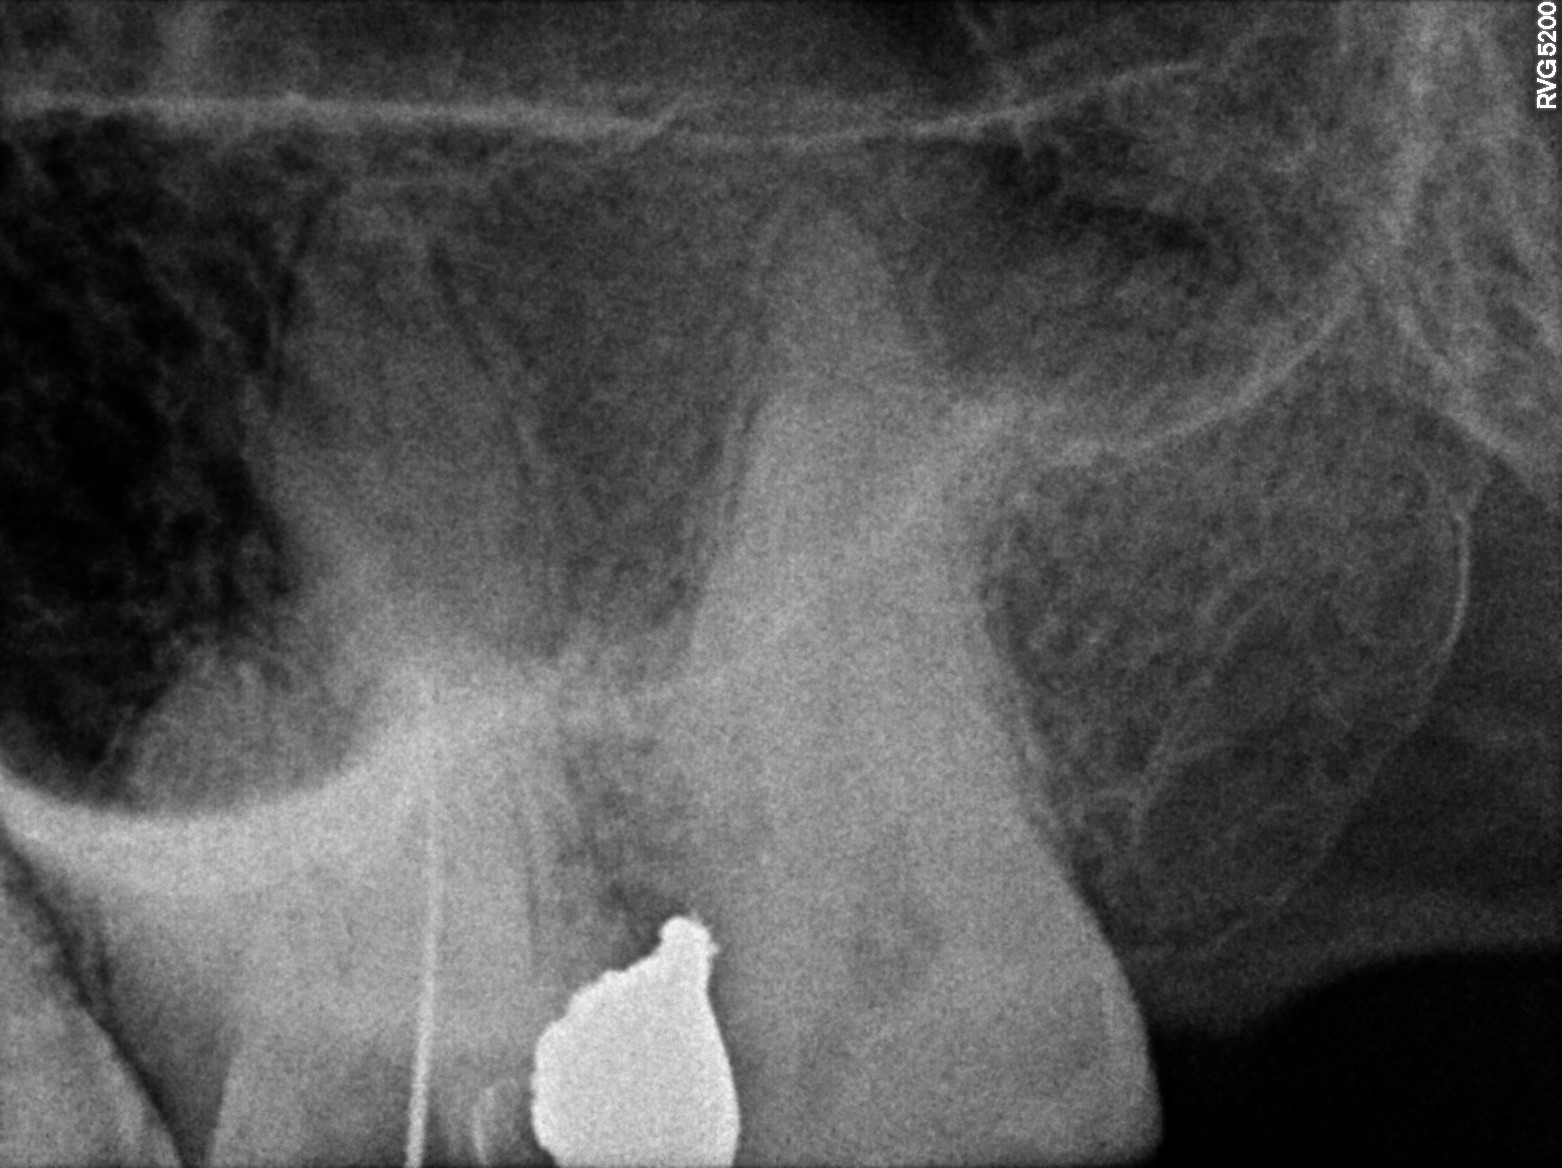

Dental Radiographs FHIR: DocumentReference · LOINC 24641-7

xray_1747409705_0.jpg

24641-7